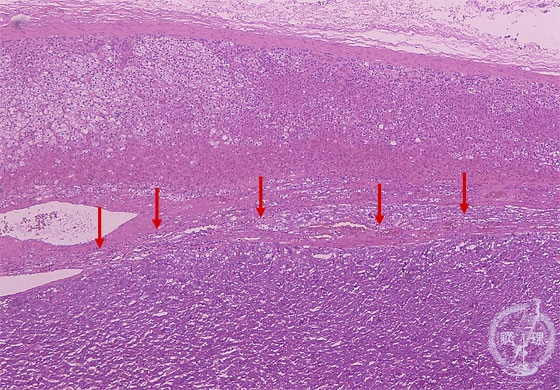

- ★(14)Pheochromocytoma

Microscopic findings (HE stain, low power view). Proliferation of the tumor cells (arrows) in the medulla of the adrenal gland.